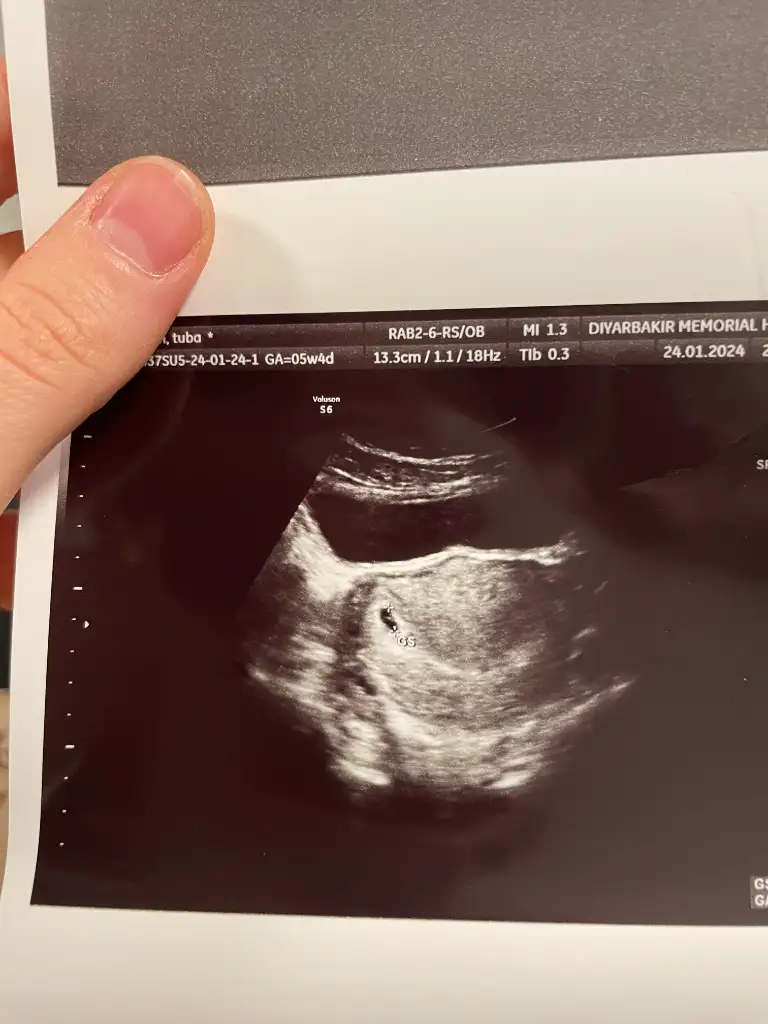

• 1000831329.webp

1000831329.webp

37,1 KB · Görüntüleme: 42